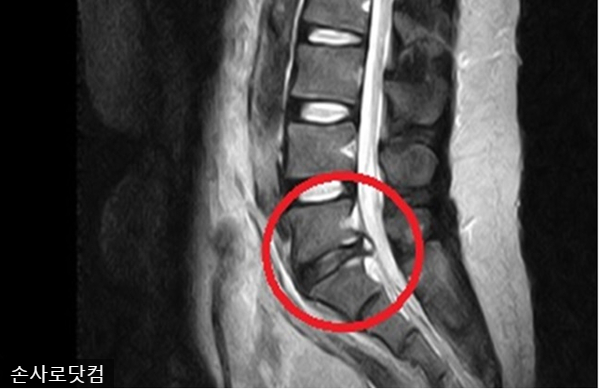

![]()

요추나 골반에 추간판 손상이 생기면 허리와 천골에 통증이 생기고 한쪽 다리에 감각이나 운동 장애가 생길 수 있다. 심하면 내장까지 영향을 미쳐 배변 조절이 어려워지는 경우도 있다. 그날은 아무 잘못도 느끼지 못할 수도 있습니다.